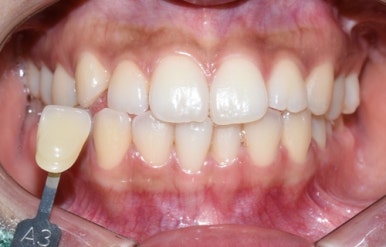

몇 달 후 환자분이 말씀하신 대로 다시 미백2회진행을 위해 오셨는데

여전히 매일 커피는 드신다고 하셨지만

그래도 처음 때와 비교하면 잘 유지되고 있는 모습이었습니다.

몇 달 동안 커피를 매일 드셨지만 그래도 처음에 비하면 잘 유지된 모습입니다.

이번에도 치아미백2회 진행하였습니다.

예전에 미백을 하신 상태이므로 이미 애초보다는 밝은 치아였지만 거기서 또 밝아진 것을 볼 수 있습니다.

(미백 진행 전 후 같은 날 사진입니다)